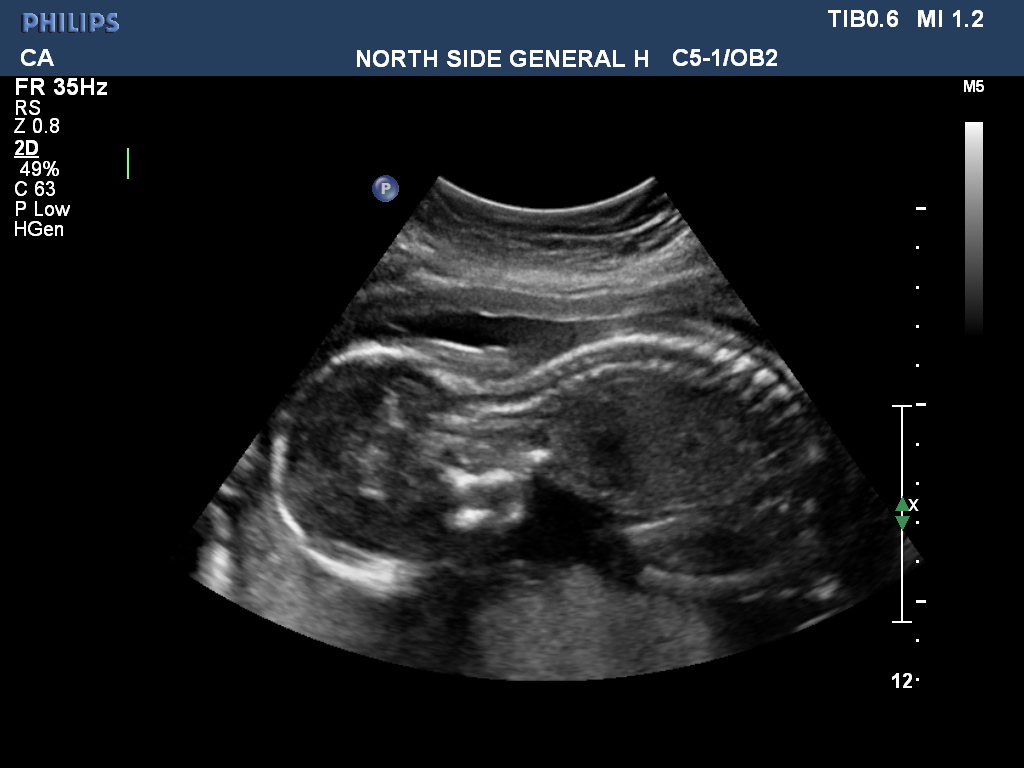

Just for fun because I don't think there are any clues here. And not sure what I'm looking at in #3 :lol: I didn't ask the tech b/c I want to be surprised since this is our last but guessing is fun :) ETA - This is from today 20 weeks 5 days.

Attachment 39422

Thanks ladies! Stupid question maybe, but the white blob under the belly in the first pic is not a penis/scrotum is it?

Doesn't look like it. I think it's likely bone given how white it looks.